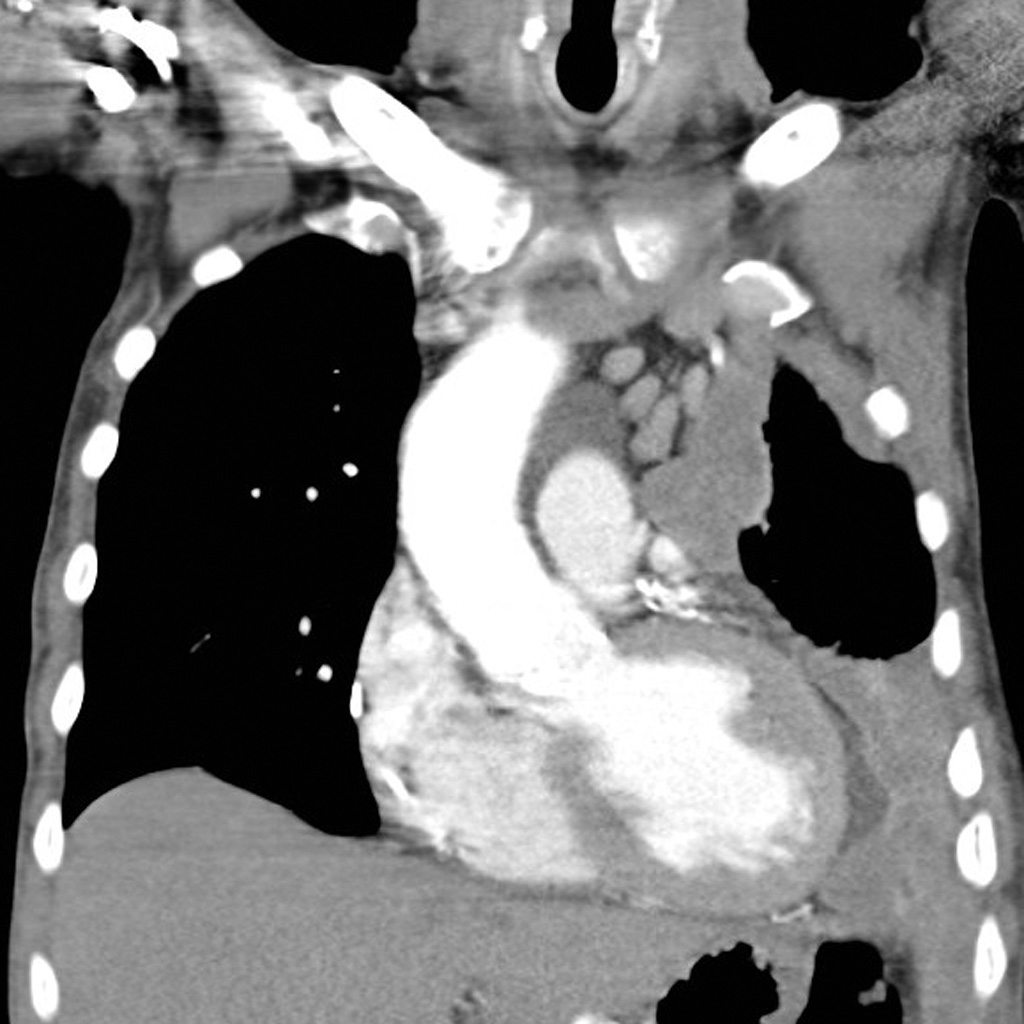

Mesothelioma is a malignant neoplasm of mesothelial cells.

Mesothelioma is strongly linked to occupational exposure to asbestos.

Mesothelioma presents with:

- Chest pain

- Dyspnea

- Recurrent pleural effusions